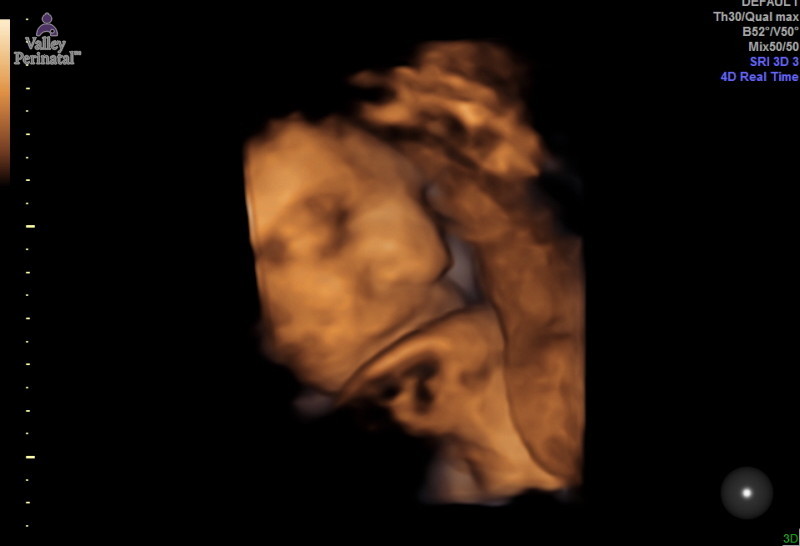

She looked so cute today when we saw her! She even smiled at us!

So if you can tell she is on the left side of the picture and the thing below her chin is her FOOT! Ya this girl is a future yoga instructor or gymnast because the whole 40 minutes her foot was up be her mouth!

That foot! Hahaha on the right is the side of her face.